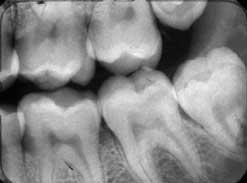

Una angulación horizontal incorrecta hace que los contactos se superpongan. Cuando se angula correctamente, los contactos están abiertos, como se muestra a continuación.